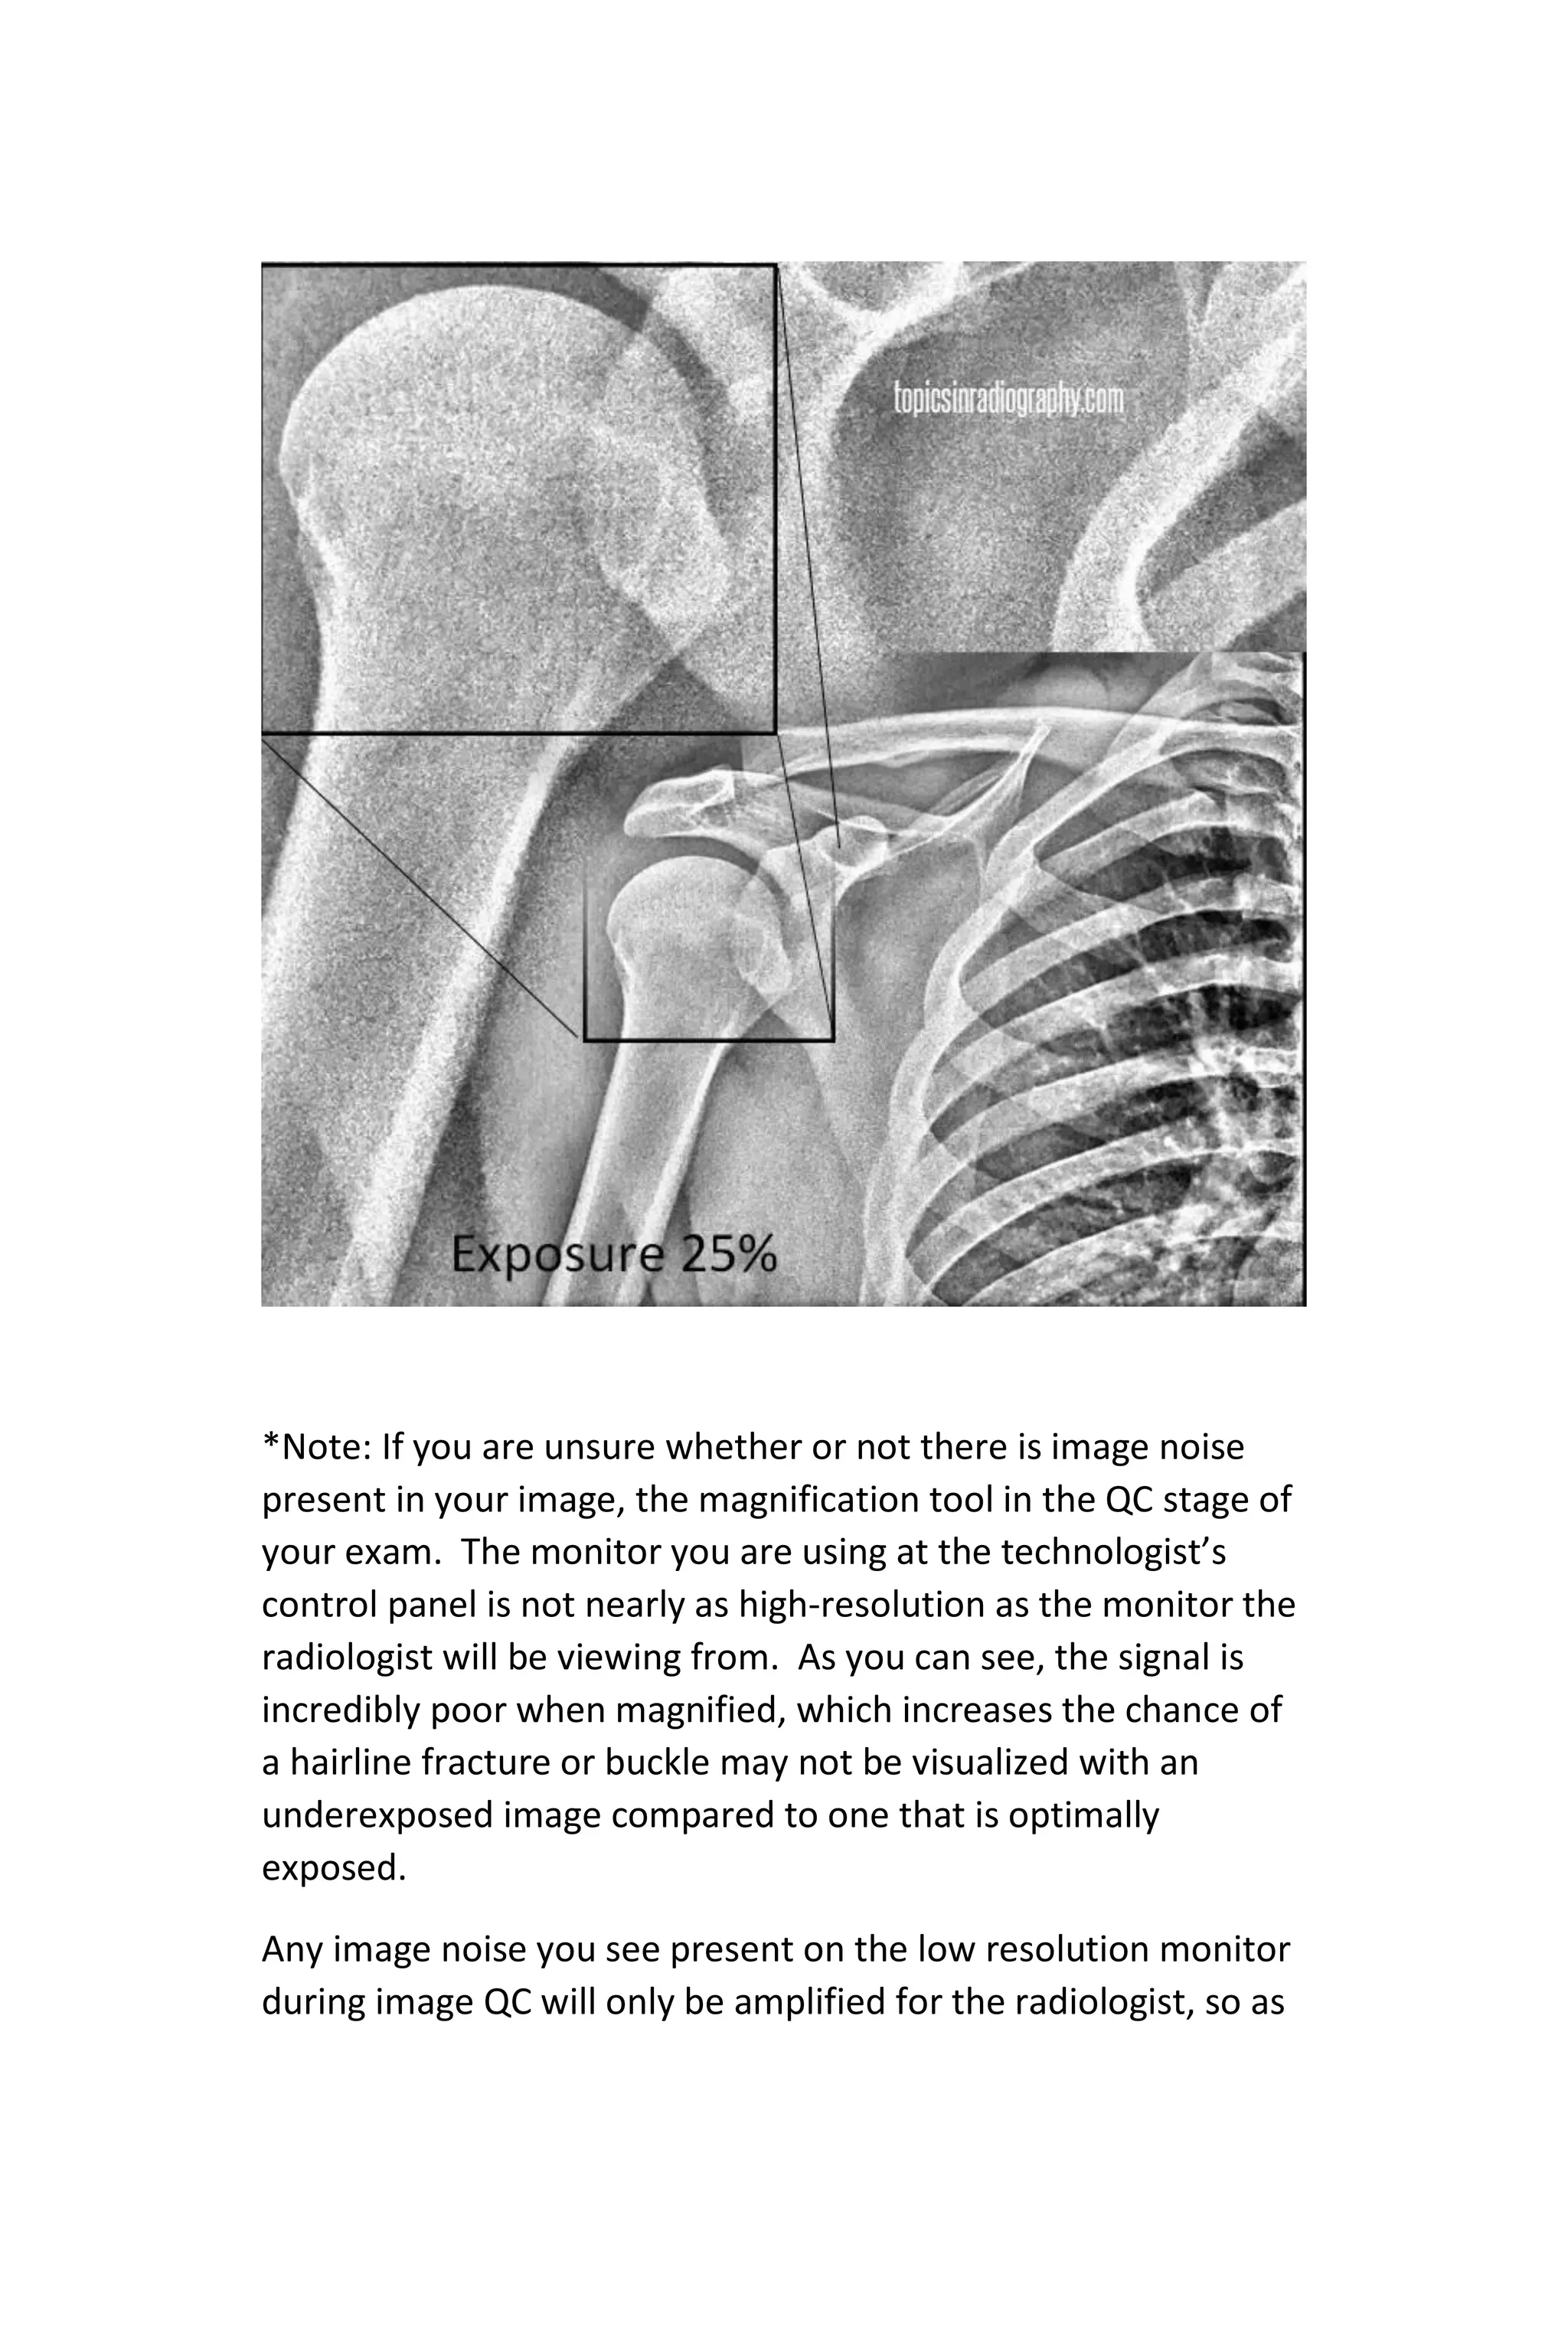

Most of the images that are underexposed will require a repeat

exposure. As a rule of thumb, I would recommend any

exposure made with less than 50% of the required exposure to

provide an optimum Exposure Indicator be thoroughly

evaluated. Though software will make this image appear

adequate, a magnified evaluation of the image is required.

*Note: If you are unsure whether or not there is image noise

present in your image, the magnification tool in the QC stage of

your exam. The monitor you are using at the technologist’s

control panel is not nearly as high-resolution as the monitor the

radiologist will be viewing from. As you can see, the signal is

incredibly poor when magnified, which increases the chance of

a hairline fracture or buckle may not be visualized with an

underexposed image compared to one that is optimally

exposed.

Any image noise you see present on the low resolution monitor

during image QC will only be amplified for the radiologist, so as

a rule of thumb, consider a repeat of noise is obvious as in the

image above.